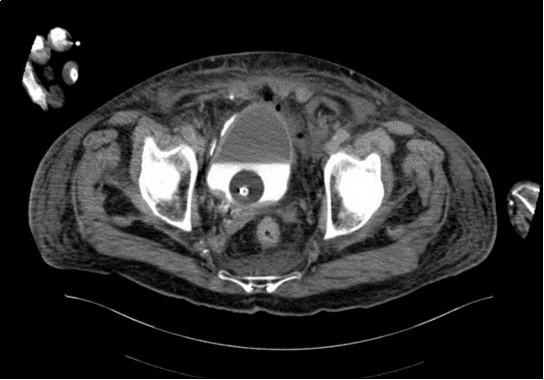

An urgent CT abdomen revealed a bladder perforation with the tip of the irrigating catheter situated in the abdominal cavity (Figure 1, Figure 2, Figure 3a,Figure 3b). This was most likely due to over-insertion of the 3-way catheter due to the extra force required because of the benign prostatic hypertrophy. He had therefore been receiving normal saline as ‘peritoneal dialysis’ with normal saline since insertion of the catheter. The catheter was withdrawn, and the patient made a full recovery.

Figure 3a.horizontal plane CT image 2

horizontal plane CT image 2